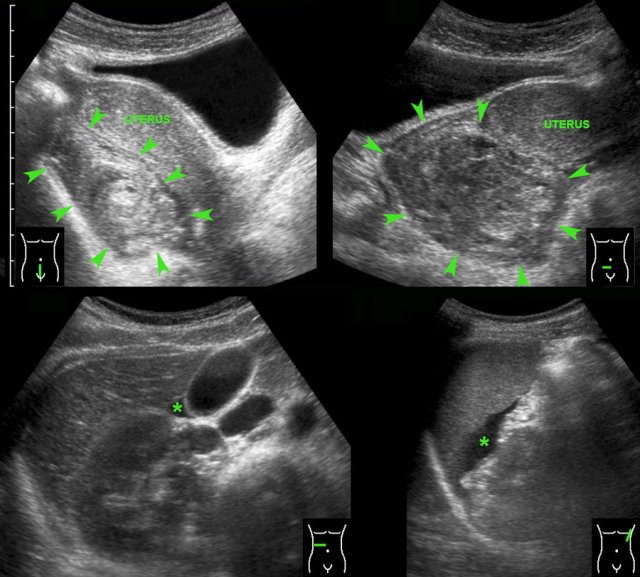

TOA case 1

Young,

very ill woman with acute LLQ pain and a CRP of 260. Left of the uterus a massively

enlarged (6 x 7 x 8 cm) ovary is found.

The individual follicles are enlarged, ill-defined

and filled with turbid fluid (pus).

Note the hyperechoic halo around this inflamed

mass.

Since

there is no apparent involvement of the Fallopian tube, strictly speaking this

is an oophoritis.

Nevertheless, usually the term of tubo-ovarian abscess is used.

TOA case 2

Young

woman presenting with severe acute abdominal pain clinically suspect for perforated

appendicitis.

Lab-findings at admission: WBC 10.6 - CRP 6 Two days later: WBC 19.7 - CRP 459

US showed a large inhomogeneous masses left and

right of the uterus, suspect for tubo-ovarian abscess (TOA).

There

was also a paralytic ileus with secondary wall thickening of small bowel (b.) and

hyperechoic preperitoneal and mesenterial fat.

Puncture of a little ascites yielded

2 cc of yellow, turbid fluid.

CT

confirmed the US findings but additionally demonstrated a pyosalpinx (p.)

within the tubo-ovarian mass on the right side. Antibiotics are started intravenously.

Two

days later PCR of both cervical and urethral probes as well as the punctured

fluid were positive for Chlamydia.

Rapid recovery with only antibiotics.